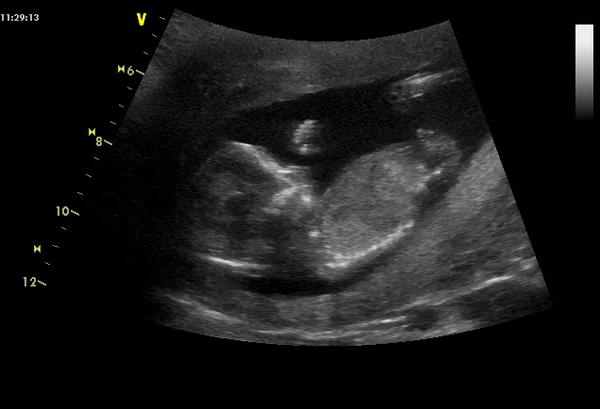

tak holky kde jste kdo? nerikejte, ze nemate nejake novinky? Marcel co ty? vsechno ok? jinak mám za sebou screening a pan doktor nam pogratulovat k ukazkovému miminku, má prý všechno naprosto v pořádku, jsem tak moc rada emoticon, ale co to je nerekl, ze pry za 14 dni to bude jasne, takze si pockam, ale nevadi, hlavne, ze je zdrave

@evcann jeeee, to je krasnoucne mimino 🙂 moc gratuluju, jedna z dulezitych etap je za vami! Nam to pohlavi doktor taky takto odkladal, pokazdenze priste priste a ted kdyz jsme byli na velkem ultrazvuku v 21 tydnu, tak mimino sedelo na turka, takze zase nic 😀 no, holt se pripravuju na variantu, ze to bude prekvapko az do konce 😎